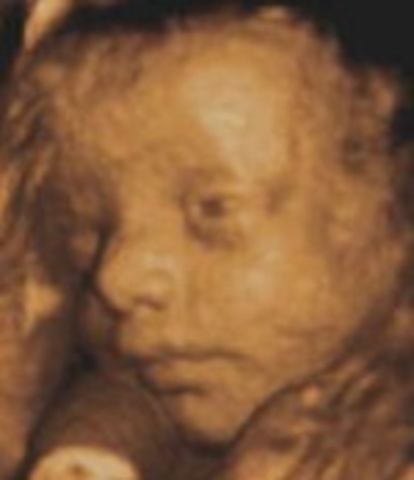

• Week 27

Week 27

This is the start of the third trimester and the look of the baby will be the same at birth. The brain is rapidly growing, and the retina of the eyes are developing.

• Week 28

Week 28

The baby is now entering REM sleep and the eyelids can open now. If this baby was born prematurely they have a 90% chance of living.